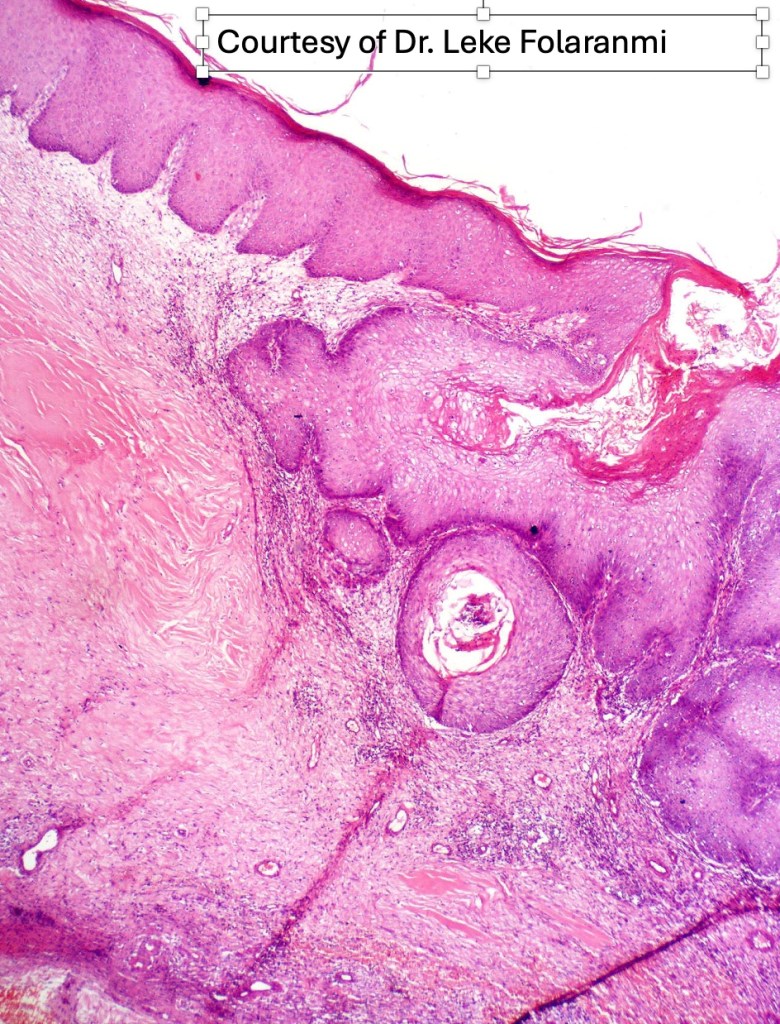

•Warty lesions with conspicuous keratin-filled sinuses (carcinoma cunniculatum due to its resemblance to a rabbit warren; Latin cunniculus- rabbit, warren)

•Epidermal verrucous hyperplasia

•Deeply penetrating bulbous processes with a pushing rather than infiltrating lower border